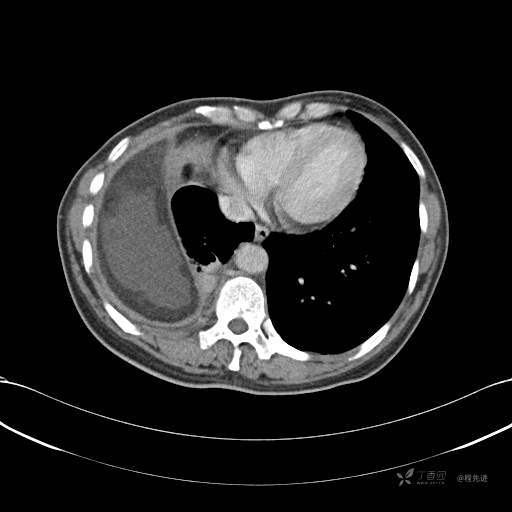

患者性别:女

患者年龄:51岁

简要病史:胸闷半年

肺淋巴管肌瘤病 (7)

乳糜胸 (8)